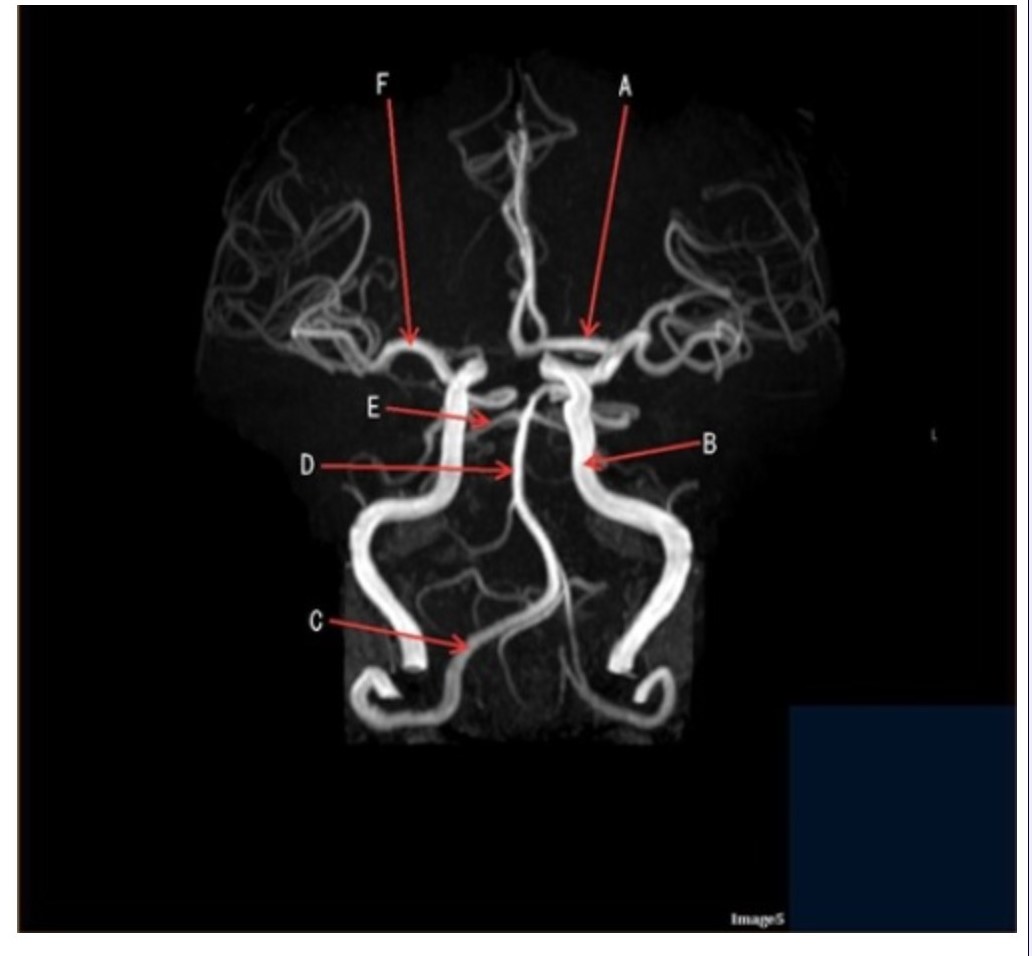

Letter D in Image 5 is pointing to:

A. Anterior cerebral artery

B. Internal carotid artery

C. Basilar artery

D. Posterior cerebral artery

E. Middle cerebral artery

Letter F in Image 5 is pointing to:

A. Anterior cerebral artery

B. Internal carotid artery

C. Basilar artery

D. Posterior cerebral artery

E. Middle cerebral artery

Image 5 is an example of an:

A. MRI brain

B. MRV sagittal sinus

C. MRS single voxel

D. MRA Circle of Willis

Letter B in Image 5 is pointing to:

A. Anterior cerebral artery

B. Internal carotid artery

C. Basilar artery

D. Posterior cerebral artery

E. Middle cerebral artery

Letter C in Image 5 is pointing to:

A. Vertebral artery

B. Internal carotid artery

C. Basilar artery

D. Posterior cerebral artery

E. Middle cerebral artery

Letter E in Image 5 is pointing to:

A. Anterior cerebral artery

B. Internal carotid artery

C. Basilar artery

D. Posterior cerebral artery

E. Middle cerebral artery

Letter A in Image 5 is pointing to:

A. Anterior cerebral artery

B. Internal carotid artery

C. Basilar artery

D. Posterior cerebral artery

E. Middle cerebral artery